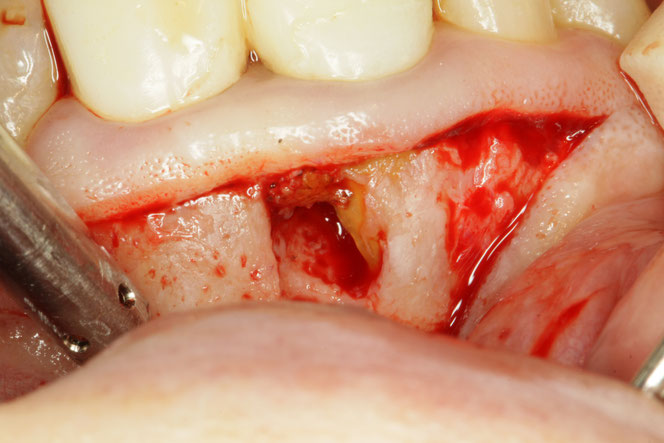

今回のケース

矯正治療後に奥歯の歯ぐきが2~3ミリ退縮。

その結果、露出した根の一部が虫歯になっていました。

「歯並びはきれいになったのに、今度は虫歯…」

そんな状態です。

✔ 虫歯の除去

✔ 歯ぐきの再生治療

を組み合わせて行います。

単にレジン(白い詰め物)で埋めるだけでは、

再び虫歯になる可能性があります。